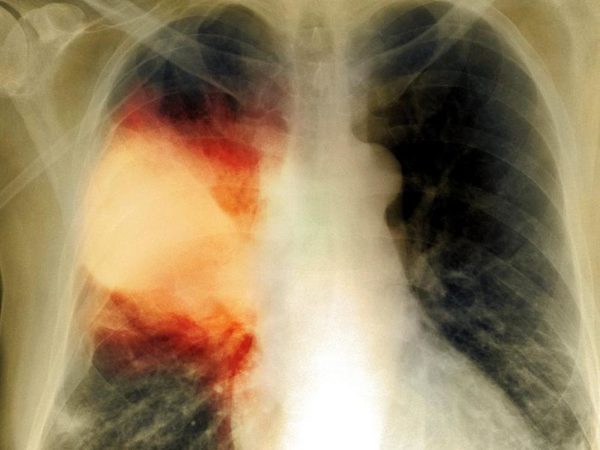

— на рентгенограмме грудной клетки, в области легких видно затемнение, как на фото ниже:

- рентгенография легких;

От других лёгочных патологий бронхиты отличаются в первую очередь областью локализации воспалительного процесса. При этом заболевании поражается слизистая оболочка бронхов, тогда как у больного пневмонией затрагиваются альвеолярные участки лёгких. На рентгене очаги бронхита чаще всего визуализируются слабо.